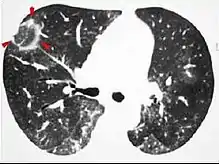

Imaging

The chest x-ray is distinctive with features that appear similar to an extensive pneumonia, with both lungs showing widespread white patches. The white patches may seem to migrate from one area of the lung to another as the disease persists or progresses. Computed tomography (CT) may be used to confirm the diagnosis. Often the findings are typical enough to allow the doctor to make a diagnosis without ordering additional tests.[19] To confirm the diagnosis, a doctor may perform a lung biopsy using a bronchoscope. Many times, a larger specimen is needed and must be removed surgically.

Plain chest radiography shows normal lung volumes, with characteristic patchy unilateral or bilateral consolidation. Small nodular opacities occur in up to 50% of patients and large nodules in 15%. On high resolution computed tomography, airspace consolidation with air bronchograms is present in more than 90% of patients, often with a lower zone predominance. A subpleural or peribronchiolar distribution is noted in up to 50% of patients. Ground glass appearance or hazy opacities associated with the consolidation are detected in most patients.

Unusual presentations of organizing pneumonia

While patchy bilateral disease is typical, there are unusual variants of organizing pneumonia where it may appear as multiple nodules or masses. One rare presentation, focal organizing pneumonia, may be indistinguishable from lung cancer based on imaging alone, requiring biopsy or surgical resection to make the diagnosis.[20]